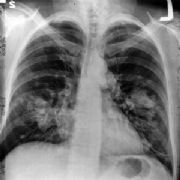

BORNHOLM - Patientforeningen Lungekræft har søgt Bornholms Regionskommune om støtte på 10.000 kroner til opstart af en lokalafdeling på Bornholm.

Formålet for Patientforeningen Lungekræft er, at støtte og vejlede lunge- og lungehindekræftramte og deres pårørende gennem et netværk af ligestillede kontaktpersoner, at arbejde for forbedring af forholdene ved aktivt at deltage i den offentlige debat om sygdommen.

Foreningen oplyser, at der på Bornholm er ca. 50 patienter med lungekræft samt deres pårørende. For tiden har foreningen otte medlemmer fra Bornholm. Foreningen ønsker at tage initiativ til at der etableres en lokalafdeling på Bornholm ved at invitere til et offentligt møde på Bornholms Hospital med besøg af læger fra Rigshospitalet.